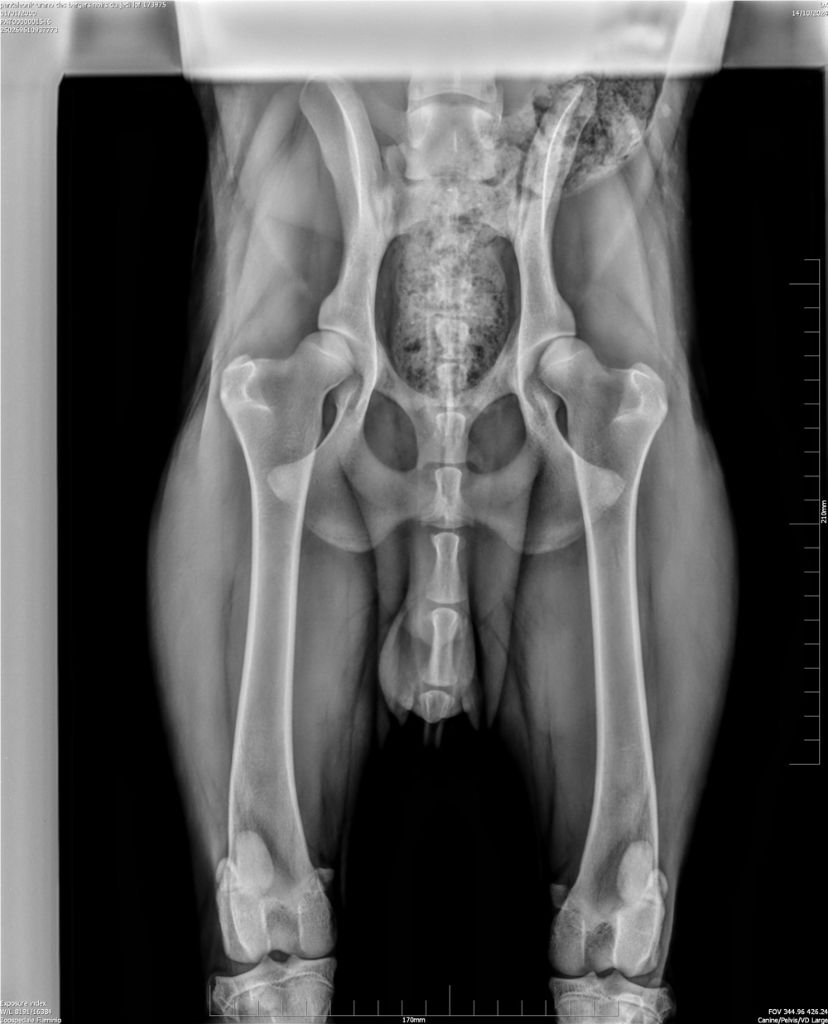

Chien Berger de Beauce Urano Des Bergers Noirs Du Jedi

LOF/173975